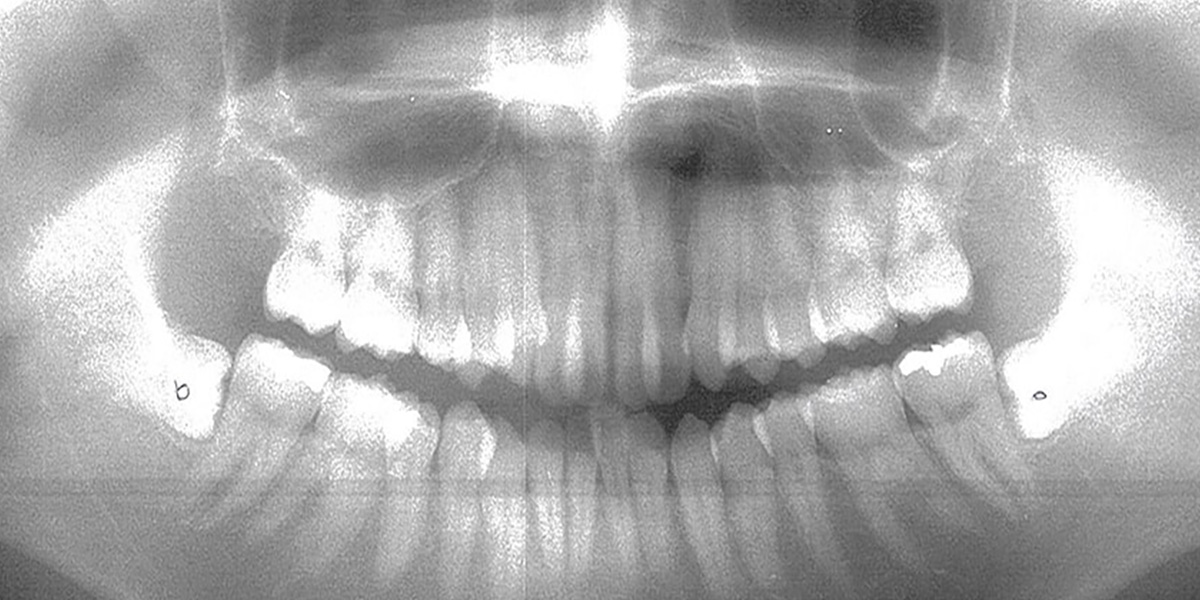

■ レントゲン(治療後)